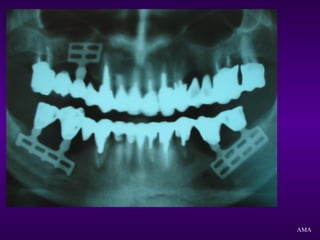

EXAME RADIOGRÁFICO

Radiografias Periapicais

Radiografia Panorâmica

Radiografia de Perfil

Planigrafias

Tomografia Computadorizada

AMA

ACIDENTES

ANATÔMICOS

Assoalho da fossa nasal

Canal e forame nasopalatino

Seio Maxilar

Nervo alveolar inferior

Forame mentoniano